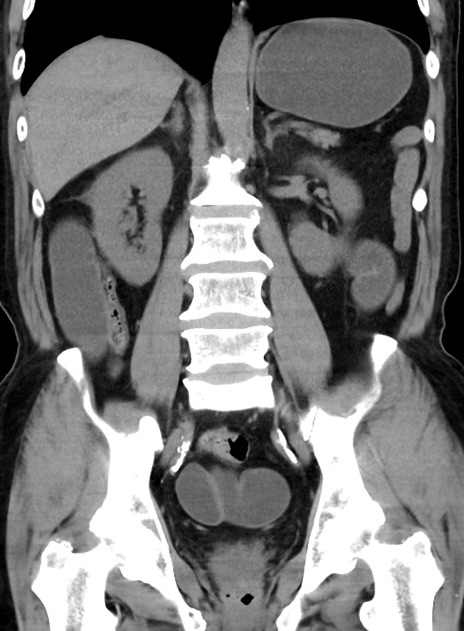

症例38(冠状断像)

【症例】70歳代 男性

【主訴】腹痛・嘔吐

【現病歴】昨晩より、嘔吐・腹痛あり。今朝になっても嘔吐あり。来院。

【既往歴】心臓バイパス手術、開腹胆摘、腸閉塞

【身体所見】BP 107/71mmHg、HR 116/min、腹部:平坦、軟、下腹部に軽度圧痛あり。反跳痛なし。

【データ】WBC 15100、CRP 0.32